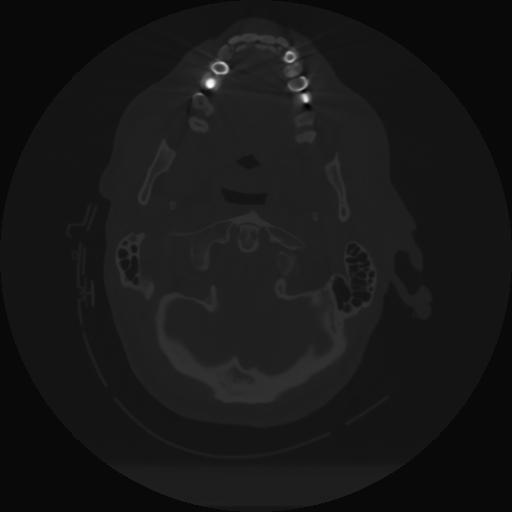

12 P.BLANDAS,,Vol,0.5,P.BLANDAS,,